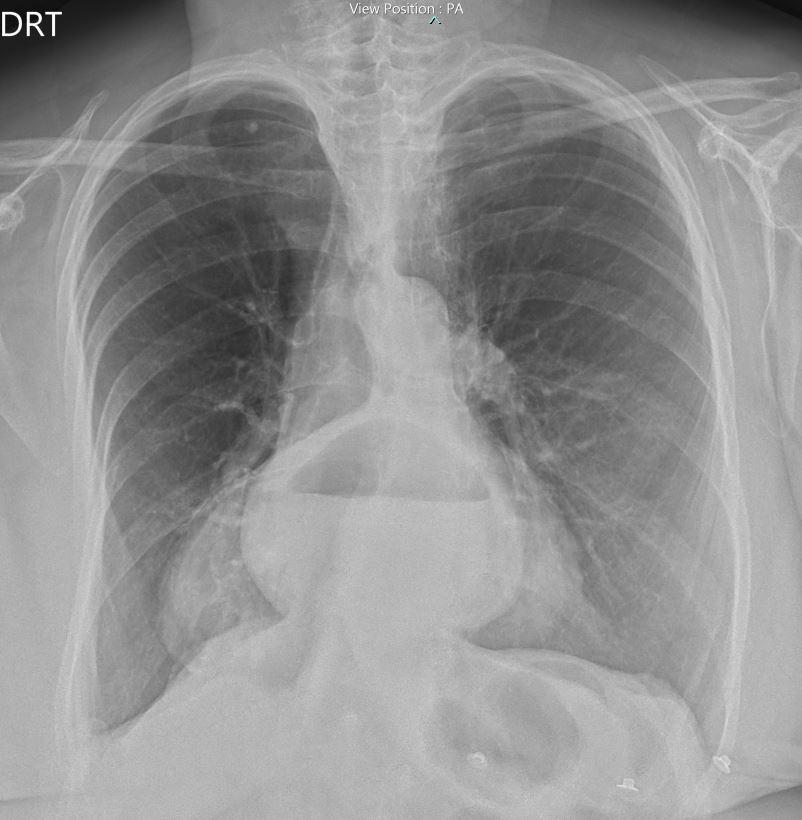

As guidelines de 2025 da American College of Cardiology /American Heart Association/American College of Emergency Physicians /National Association of EMS Physicians / Society for Cardiovascular Angiography and Interventions2 mantêm os critérios das anterior guidelines de 2023, relativamente à interpretação de supra e infra ST (Figura 2).

A evidência científica demonstra que a realização extra-hospitalar de ECG de 12 derivações permite uma redução significativa do tempo total de isquemia (desde o início dos sintomas até à instituição da

terapêutica de reperfusão), sendo este um elemento fundamental para estabelecer o diagnóstico, estratificar o risco isquémico e definir a estratégia terapêutica. O ECG fornece informação importante acerca da localização e extensão da lesão miocárdica, particularmente no EAMCST. Estes aspetos são de extrema importância, uma vez que podem influenciar o prognóstico e, em alguns casos, determinar a escolha da terapêutica mais adequada. No ECG de 12 derivações a elevação persistente do segmento ST é o grande parâmetro de indicação para terapias de reperfusão emergente, há casos em que podem não se verificar estas condições. Nomeadamente no enfarte da parede posterior ou do ventrículo direito, de forma isolada. A realização das derivações adicionais posteriores e direitas, em particular, as derivações V7, V8 e V9 e V3R-V6R, respetivamente, que demonstram alterações compatíveis com isquemia aguda e indicação para reperfusão emergente1. Existem outros critérios e padrões electrocardiográficos (Figura 3) que são definidos como equivalentes de SCA com supradesnivelamento do segmento ST, como o padrão de “De Winter”, “Síndrome de Wellens” e o infradesnivelamento do segmento ST generalizado com supraST em aVR, indicativo de doença do tronco comum2,3,4,7,10,11,12